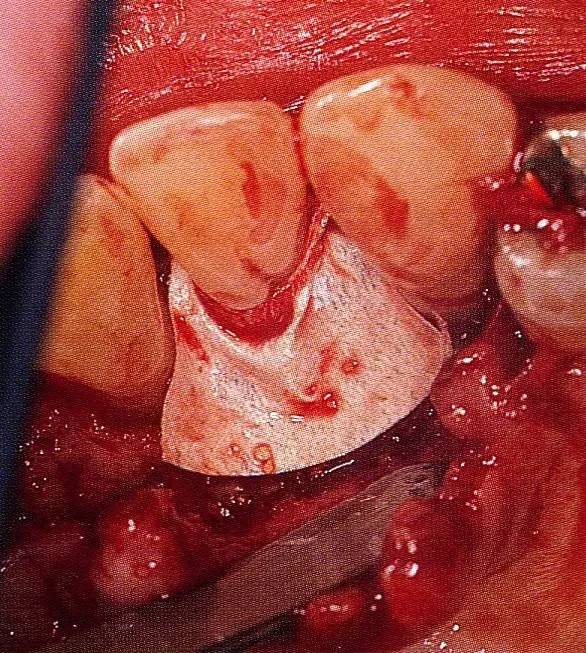

案例3   針對3壁性垂直性骨缺損使用非吸收性膜進(jìn)行再生治療,再翻瓣時進(jìn)行骨形態(tài)修整的病例。

▲圖7-1  左下6近中可觀察到3壁性垂直性骨缺損。此病例考慮到齦瓣供血關(guān)系,在前磨牙部位進(jìn)行了減張切開,沒有進(jìn)行縱切開。并利用刮治器、牙周外科用車針進(jìn)行了徹底的骨缺損部位搔刮。